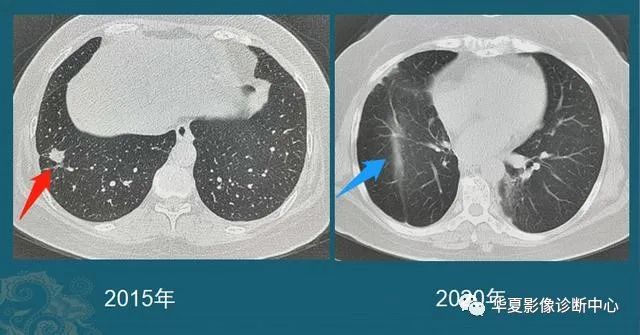

没想到我这么大岁数,切掉一个肺叶的十年后,再次做这么复杂的手术还这么顺利。 D大爷今年72岁,10年前曾行左肺上叶切除+淋巴结清扫术,手术标本病理为腺癌,术后给予了四次化疗。当时的胸部CT即可见右肺上叶小结节影,术后定期复查,病灶缓慢增大,一度略有缩小,此后再次逐渐增大。结合患者一直随访的影像学资料,杨如松院长考虑为右上肺新发恶性肿瘤。 2015年胸部CT 2020年胸部CT 虽然患者及其家属手术的意愿非常强烈,但此手术难度较高,原因在于: 1.患者年龄较高,手术风险大。 2.患者10 年前肺癌手术切除左边肺的一半,肺功能丧失较多。 3.病灶在右上肺的深部,切除有一定的难度。 为了保证患者术后的生活质量,我们不能够做肺的楔形切除这样的简单肺手术,而需要行肺段的切除。 EDDA重建提示病灶位置深 如果放在以前该患者就只能做做放化疗等保守治疗了。幸亏南京胸科医院目前引进了各种国内乃至国际上的先进技术。 如EDDA术前三D成像技术;只有单一3cm长切口的单孔胸腔镜技术;近红外荧光镜肺段、亚肺段精准定位技术等。 有了这些技术,杨如松院长心中有了底气。杨院长根据病人的情况设计手术方案,尽量减轻手术创伤,让接受第二次肺部复杂手术的高龄病人能够耐受,并且在术后能够顺利恢复。 根据术前EDDA三维重建,患者进行了单孔荧光胸腔镜S1a+2a切除术,术中先用ICG反染法确定段间面,再用膨胀萎陷法印证段间面,这保证了手术切除的精准性。 患者术中快速病理为贴壁型腺癌,这也印证了杨如松院长术前对患者肺结节良恶性的判断。 术后5天,D大爷非常顺利的出院了。出院前开心的窦大爷连声感谢杨如松院长:没想到我这么大岁数,切掉一个肺叶的十年后,再次做这么复杂的手术还这么顺利,谢谢、谢谢! 基本情况